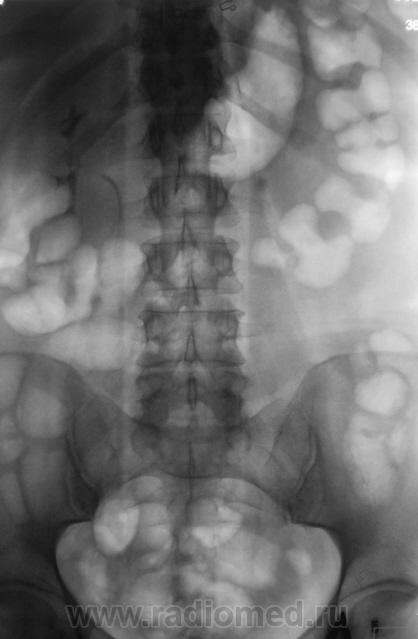

Через два дня - в\в урография......

Какие будут мнения?

Начинаю описывать в\в урографию и...где же тень конкремента? ЕЕ на прежнем месте нет....ЧЛС слева не расширена, дополнительных теней или "плюс-тени" явно не просматривается....

Начинаю мужичка "трясти как грушу"..."всплывает" обзорная урография за сентябрь 2009 года...да, там низковато захвачено...но зона конкремента попала...а его....НЕТ!!!!!!!!!!!!!!!! Не мог же он вырасти за каких то полгода до ТАКИХ размеров.